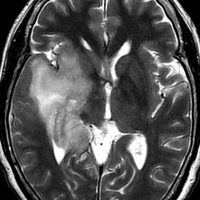

若い成人です,認知機能障害で発症しました。この画像を見るからに悪性神経膠腫,少なくともグレード3のグリオーマであることは明白です。しかし,グレード4膠芽腫あるいはグレード3退形成性星細胞腫にしては腫瘍周辺浮腫が軽すぎます。ですから,グレード3の退形成性乏突起膠腫 AO かも。認知機能の回復と温存を考量して,脳梁損傷と前交連損傷を避けて,右上前頭回と帯状回腫瘍を摘出しました。

左は術後のT1強調ガドリニウム増強像で,残存腫瘍がわかります。この腫瘍に対してICE (IFO/CDDP/VP-16) 化学療法を1コースしました。右側のMRIが1ヶ月後の画像です。このように1p/19q欠失のある退形成性乏突起膠腫は,化学療法感受性がとても高い悪性グリオーマです。ですから,手術で後遺症を残さないように,勢い込んで腫瘍を摘出しようとしないことが大切です。光顕診断はAOで,後々の解析で1p/19q codeletion でした。